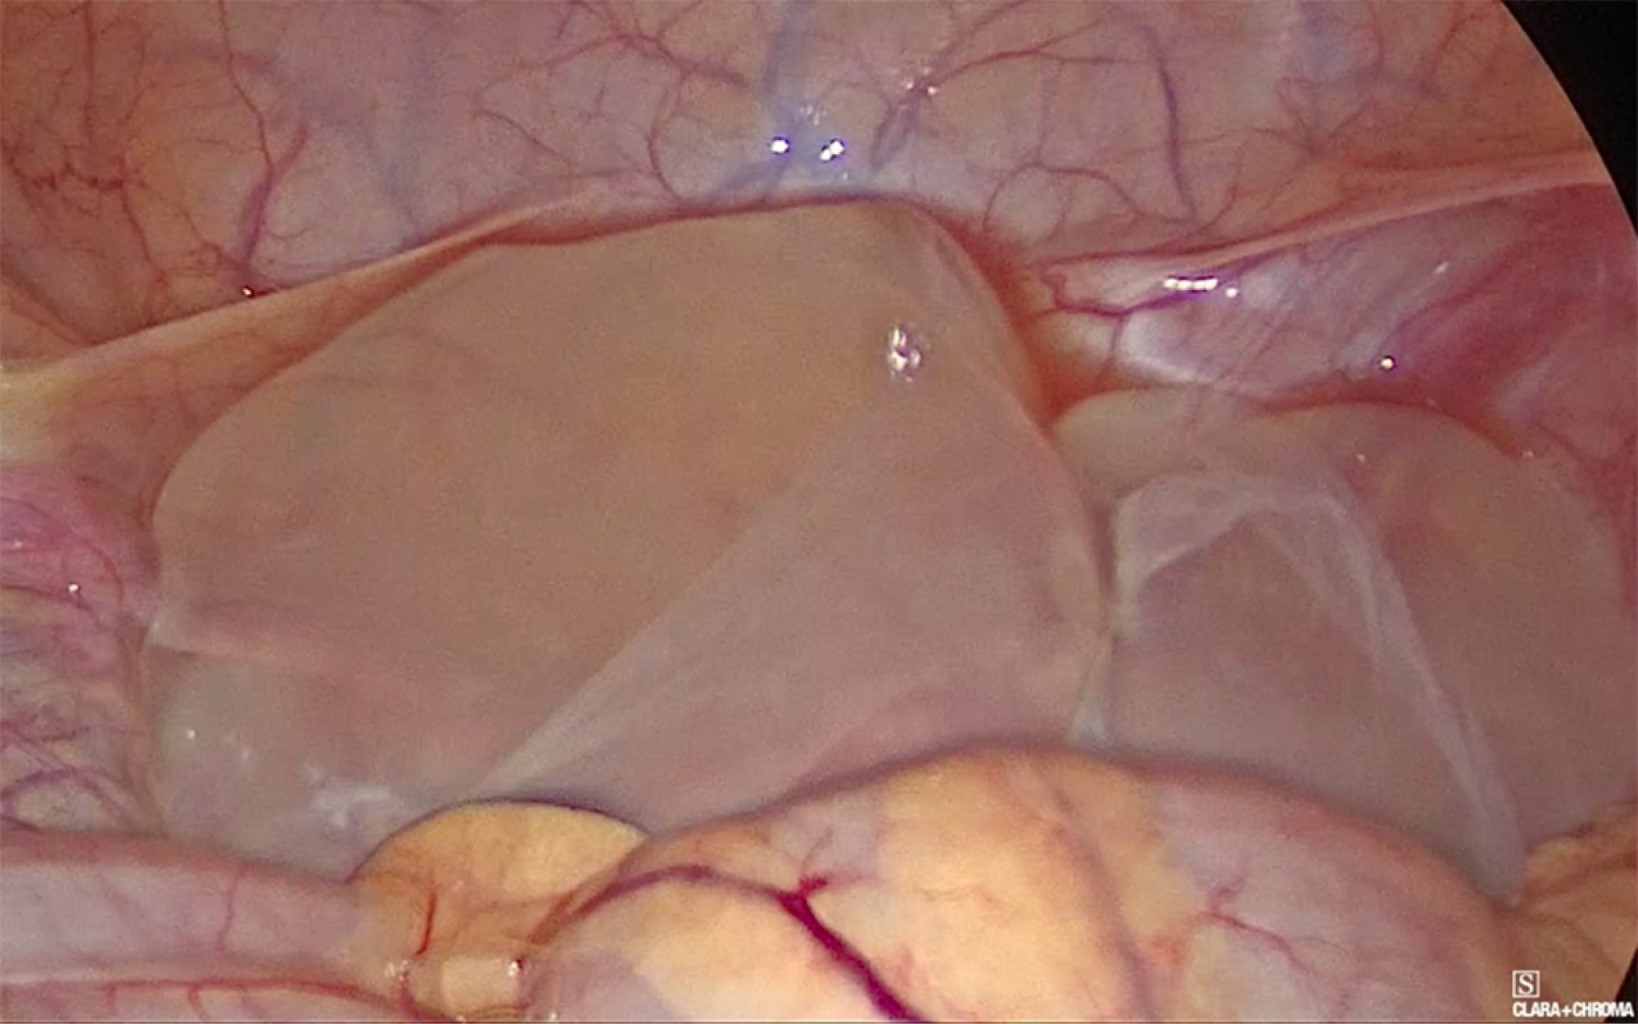

Se colocó trocar umbilical de 10 mm con lente de 30 grados, dos más de 5 mm en ambas fosas iliacas, encontrando en pelvis cuatro quistes de diferentes tamaños, siendo el mayor de 12 cm aproximadamente, otros de 7, 5 y 4 cm, con paredes delgadas y lisas, traslucidos, con contenido líquido seroso, dos sueltos en pelvis (Figuras 3 y 4) y dos adheridos ligeramente a ovario y trompa izquierda, retirados con bisturí armónico (Figura 5). Se puncionó con aguja, extrayendo de cada uno líquido seroso para estudio histopatológico y citoquímico. Se extrajeron las cápsulas en su totalidad; ovarios y útero, así como el resto de la cavidad sin alteraciones, se tomó biopsia de peritoneo y epiplón mayor. Se lavó pelvis y revisó hemostasia. La paciente cursó con evolución favorable, egresando a las 24 horas del procedimiento.

Figura 4